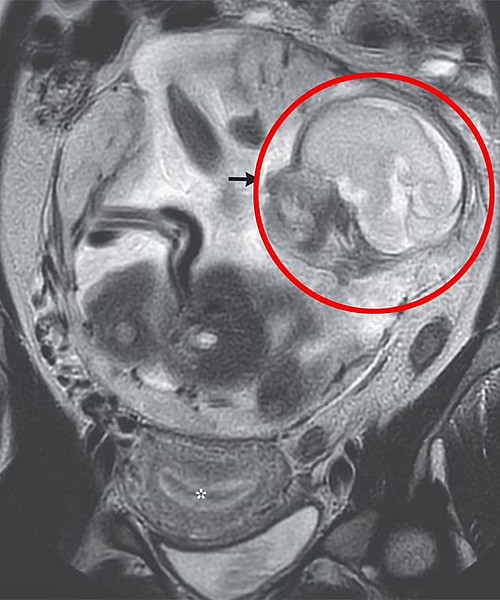

Các bác sĩ cho biết đây là hiện tượng rất hiếm gặp bởi vì thường các ca thai ngoài tử cung không thể phát triển đến tuần thứ 23 và sẽ tử vong rất sớm. Nhưng kết quả chụp chiếu của người phụ nữ Ấn Độ này cho thấy một bào thai "có hình dạng bình thường" ở khoang bụng, trong khoảng trống giữa dạ dày và ruột.

Các bác sĩ ghi nhận em bé nằm trong khoang phúc mạc, khu vực chứa các cơ quan quan trọng, với nhau thai gắn vào đỉnh xương chậu. Dù hiếm, trường hợp này vẫn có thể xảy ra nếu thai nhi bắt đầu phát triển trong ống dẫn trứng hoặc buồng trứng. Theo thời gian, khối bào thai vỡ ra, cho phép thai nhi "trốn" vào trong khoang phúc mạc.